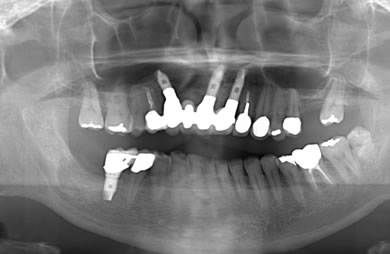

治療前

• 治療前